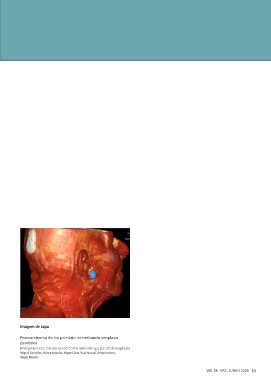

Imagem de capa

Porocarcinoma écrino primário mimetizando neoplasia

parotídea

Malignant eccrine porocarcinoma mimicking a parotid neoplasia